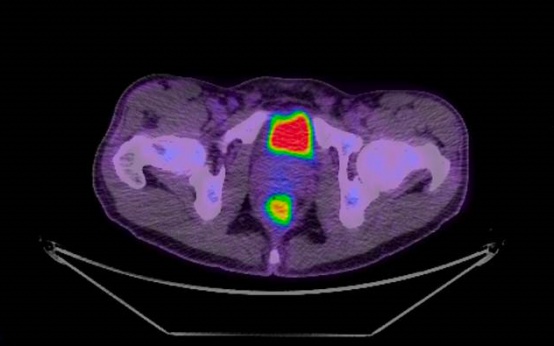

A Peter Mac-led clinical trial has found combination PET/CT scans are better at investigating the causes of prolonged fever in blood cancer patients than conventional CT scans. The randomised multicentre trial found patients who were given a combination FDG-PET/CT scan instead of a conventional CT scan were able to be given more targeted treatments. This reduced the use of broad-spectrum antibiotics – and also time spent in hospital. A combination FDG-PET/CT scan is a combined positron emission tomography (PET) scan which produces images of how organs or tissues inside the body use sugar, a key fuel for the body's organs, with a computed tomography (CT) scan which provides more anatomical information. FDG, or fluorodeoxyglucose, is the sugar compound used as the radioactive tracer in the PET scan. "A combination PET/CT scan allows us to rule in and rule out important diagnoses better than using conventional CT imaging," says infectious diseases physician Dr Abby Douglas, who was the investigator running the trial. "That's because it is both more sensitive at picking up the site of the infection causing the fever, and ruling out other important causes of fever." Prolonged or recurrent fevers are a serious problem for blood cancer patients because the patients often have low levels of neutrophils – a type of white blood cell – that help them fight off infection. Without enough of these defender cells, a fever left untreated can quickly lead to sepsis and even death. "The issue in this patient group is that we often do not know what is causing the ongoing fever," says Professor Monica Slavin, who was the Principal Investigator on the trial. "We worry about various types of infection, but there are other reasons for fever that don't need antibiotics." Without a clear diagnosis, patients will often be given a protracted course of broad-spectrum antibiotics which heightens their risk of developing antibiotic resistance, and can also do long-term harm to their gut microbiome. "It's both better for the patient and the healthcare system if we can pinpoint what is causing a fever so we can optimally treat it, and not use unnecessary broad-spectrum antibiotics," says Professor Karin Thursky, a senior investigator on the trial. The researchers conducting the trial also found the patients who were given a combination PET/CT scan had a shorter stay in hospital. "Getting out of hospital sooner is really important for patients who spend long and repeated stints here, and will likely improve their quality of life," Dr Douglas says. It also reduces their risk of healthcare-associated complications and the cost of their care. While a combination FDG-PET/CT scan costs the healthcare system approximately $1,000 that would likely be offset by the reduced time a patient is in hospital, and will be examined further in future research. Results from the trial were published in The Lancet Haematology today. The trial was conducted by Peter Mac clinical researchers from the Infectious Diseases, Haematology and Nuclear Imaging departments, in collaboration with colleagues from the University of Melbourne and the Royal Melbourne Hospital. Image: PET scan of the rectum showing site of infection as the lower orange spot. Contact For more information or to arrange an interview, call the Communications team on 0417 123 048. About Peter Mac Peter MacCallum Cancer Centre is a world-leading cancer research, education and treatment centre and Australia’s only public health service solely dedicated to caring for people affected by cancer.